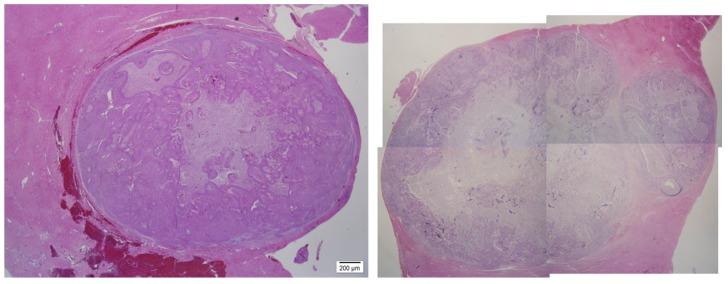

Establishment of metastatic liver carcinoma model by implanting AX7 cells into rabbit liver, and its histological findings.

: Progression of metastatic liver carcinoma from any original cancer is aggressive and the prognosis is very poor. Therefore the new model that is easily approachable to study the propagation and prognosis of metastatic liver carcinoma is necessary. The aim of this study is to confirm the tumor formation and metastatic activity of anaplastic thyroid cancer and to support the research basis for the next generation cancer treatment that is to be developed, by carrying out additional experiments like cytokine stimulation. We investigated sequential findings of immunohistochemistry of rabbit hepatic malignancy induced by AX7 cells. : 13 rabbits implanted with AX7 cells directly into liver parenchyme with laparotomy were investigated by histopathology examination, immunohistochemistry, which is useful for the evaluation of metastatic cancer angiogenesis. Growing tissue at the edge of the mass was collected and placed in the petri dish filled with saline. After removing necrotic and fibrous tissue, tumor tissue was cut into pieces, placed in saline, and extracted during the experiment. : Tumor growth and malignancy was confirmed on the 10th day after AX7 cells were implanted into liver. Positive for VEGF staining was found in the cytoplasm or cell membrane. The scores for VEGF stained cells were moderately positive (++) on day 10, strongly positive (+++) on day 44. Ki-67-positive hepatocytes reached at 65% on day 10, at 65.78% on day 14, at 66.4% on day 30, at 67.88% on day 44. : AX7 cells implanted into liver can be used as a new rabbit metastatic liver carcinoma model and would become useful for human metastatic liver carcinoma studies. Future studies may facilitate the establishment of an effective systemic therapy for the metastatic liver cancer.

AX7 细胞植入肝脏 10 天后确认肿瘤生长和恶性。细胞质或细胞膜呈 VEGF 染色阳性。第 10 天 VEGF 染色细胞的评分呈中度阳性(++),第 44 天呈强阳性(+++)。Ki-67 阳性肝细胞在第 10 天达到 65%,在第 14 天达到 65.78%,在第 30 天达到 66.4%,在第 44 天达到 67.88%。